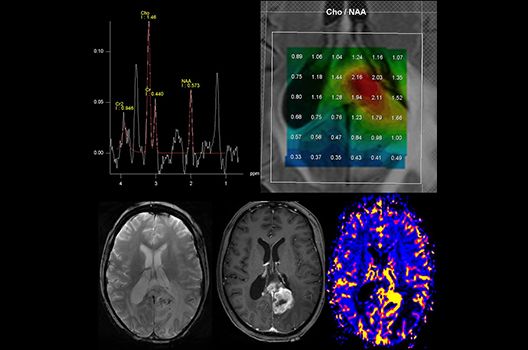

- MR-Protonenspektroskopie

Die Magnetresonanztomographie (MRT) ist ein Verfahren, bei dem durch magnetische Kräfte Bilder des Körperinneren angefertigt werden. In der Neuroradiologie können manchmal kleinste Veränderungen schwere Folgen haben; daher forschen wir an der Entwicklung hochauflösender MRT-Sequenzen, mit denen diese Prozesse und auch einzelne Nervenfaserbahnen sichtbar gemacht werden können. Darüber hinaus sind bei vielen Erkrankungen des Gehirns die Blutgefäße betroffen. Daher arbeiten wir an der Neu- und Weiterentwicklung von MRT-Sequenzen zur Darstellung der Blutgefäße und zur Blutflussanalyse (sog. „Angio-MRT“). Einen besonderen Forschungsschwerpunkt unserer Klinik stellen die MR-Protonenspektroskopie und die funktionelle MRT dar, mit denen die Analyse einzelner chemischer Substanzen im Hirngewebe oder die Darstellung ausgewählter Hirnfunktionen möglich ist.

Onkologische und Hybridbildgebung

- PET/MRT in der Neuroonkologie

Die Hybridbildgebung mittels PET/MRT spielt insbesondere in der onkologischen Bildgebung eine wichtige Rolle. Eine mögliche Fragestellung ist die Unterscheidung zwischen einem Tumorrezidiv oder therapeutisch assoziierten Veränderungen insbesondere dann, wenn diese Frage mittels MRT alleine nicht beantwortet werden kann.

Die bildgebende Diagnostik und Verlaufsbeurteilung von Tumoren des Nervensystems ist einer der klinischen und Forschungsschwerpunkte unserer Abteilung. Eine besondere Bedeutung kommt der Hybrid-Bildgebung zu. Das Universitätsklinikum verfügt über einen integrierten Ganzkörper-PET/MRT-Scanner, der die Vorteile der MRT-Bildgebung und der Positronenemissionstherapie (PET) vereinigt. Aufgrund der langjährigen klinischen Arbeit und Forschungstätigkeit mit diesem Gerät hat die Neuroradiologie Tübingen maßgeblich zur Etablierung dieses Verfahrens beigetragen. Auch weiterhin forschen wir intensiv an neuen Methoden zur frühen Einordnung von Tumoren und insbesondere Tumorrezidiven, die mit anderen Methoden häufig nicht erfasst werden können.